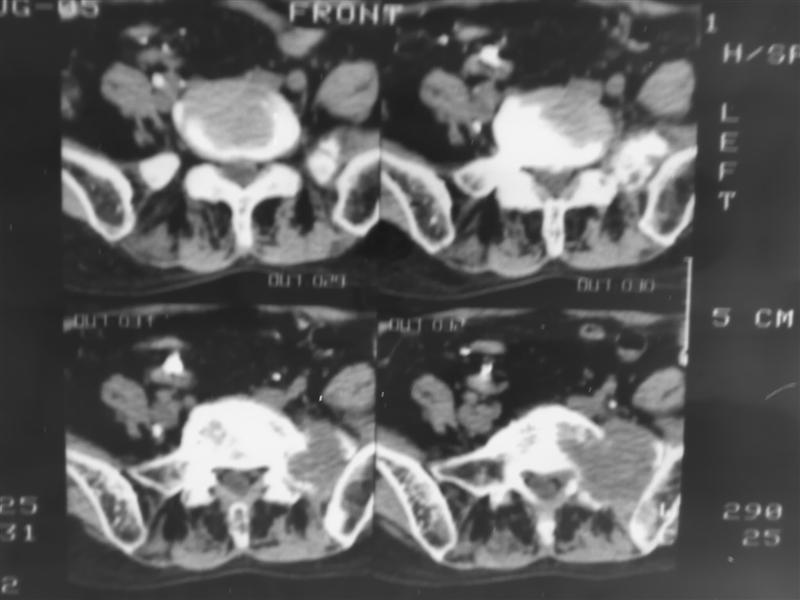

以下是引用老爱克斯新网客在2007-9-27 17:59:00的发言:[br]多个椎体及椎弓跟骨质破坏,并见软组织肿块,符合转移瘤改变,

以下是引用wqs571018在2007-9-27 16:48:00的发言:[br]支持:多发病变,骨质破坏伴软组织块影,符合转移.